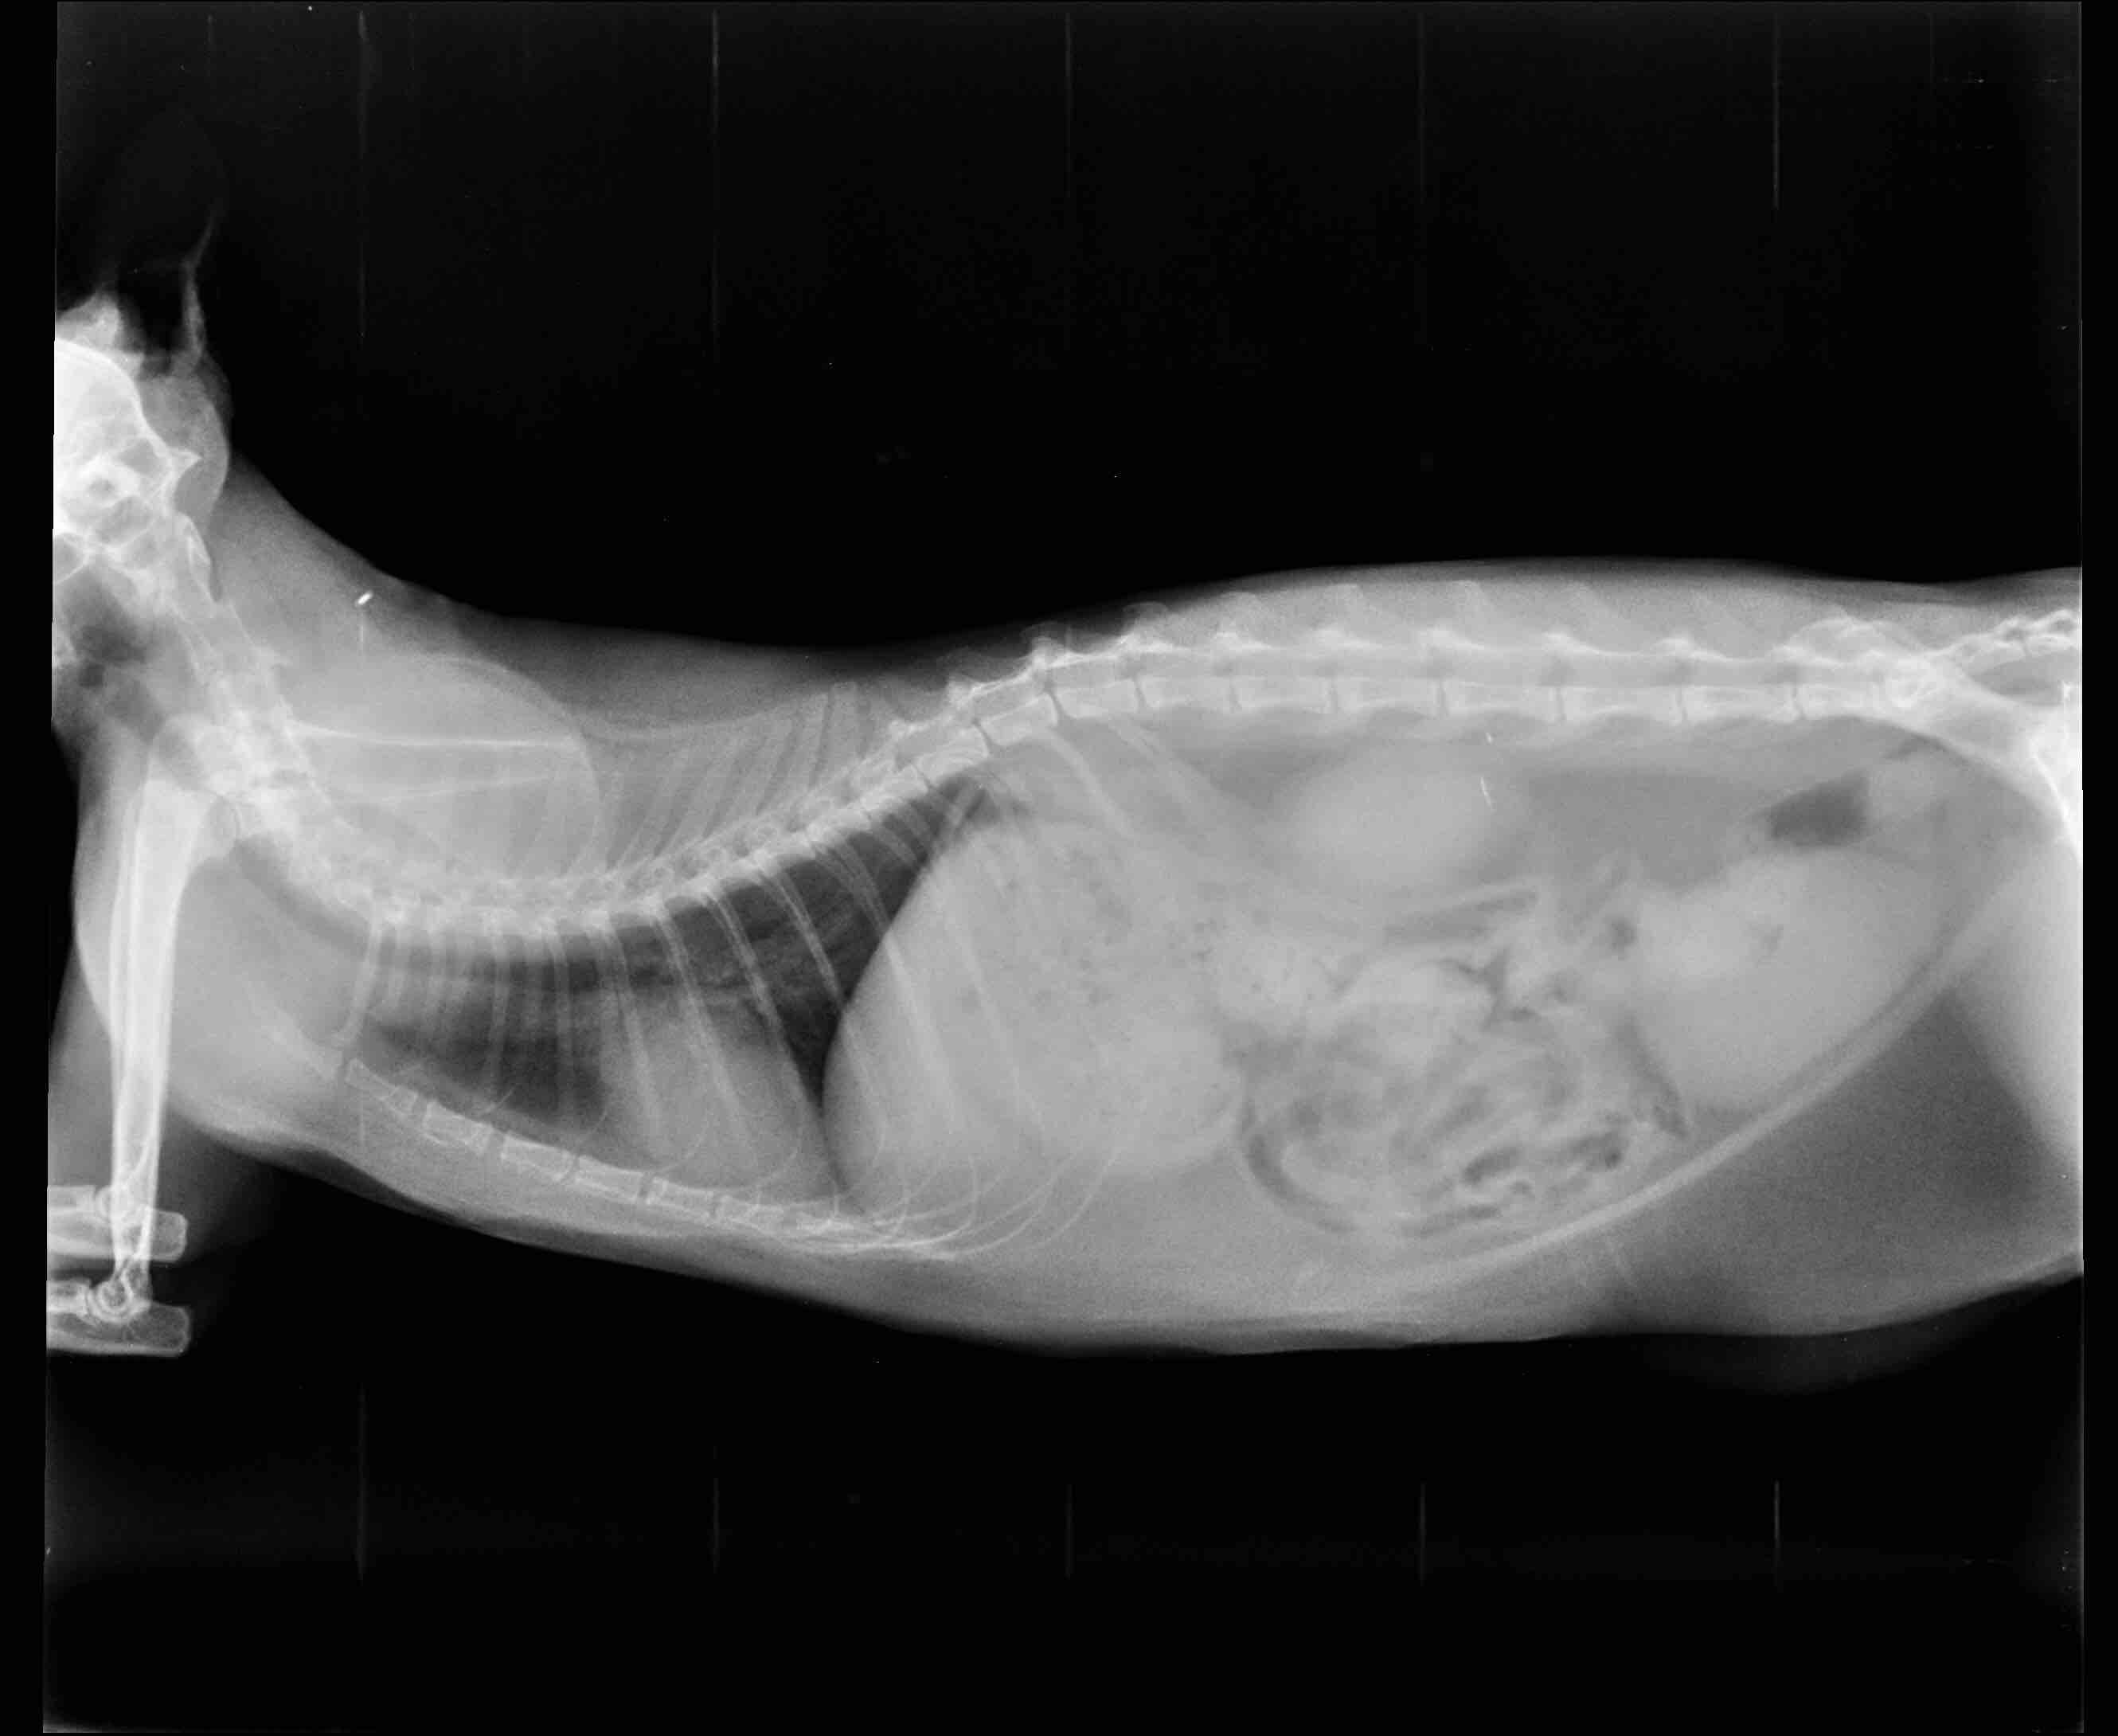

Pet's info: Cat | Mixed Breed | Female | 5 years and 10 months old

Why is her belly so big? Is she just fat? She doesn’t really exercise.

She is most definitely overweight (fat pad can be clearly seen in front of the back legs / below the abdomen). If she has any additional clinical signs I would recommend a blood test to help determine if the obesity is triggered by any medical condition or even if it has caused any problems such as liver issues. I strongly recommend you start a weight management programme such as hills metabolic or royal canin satiety to help reduce the weight (and with it risks of obesity, joint and inflammatory conditions linked with excess weight)